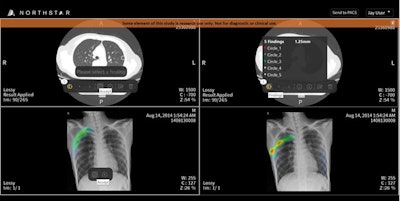

This artificial intelligence developer introduced itself to the medical imaging community at RSNA 2017 in Chicago, where it unveiled its cloud-based AI image analysis and viewing software.

The cloud visualization platform, which has been applied in other industries such as cloud 3D gaming, augmented reality, virtual reality, and autonomous driving, employs deep-learning algorithms to assess imaging data for diagnostically valuable information that is not apparent through conventional analysis, according to the vendor. It then also transmits detailed 3D/2D renderings to users on any internet-enabled device. Information and imaging tools are streamed in real-time to end users with the aid of predictive buffering.

The software supports x-ray, ultrasound, CT, MRI, 3D tomosynthesis, and digital pathology images. It has 11 international patents and received U.S. Food and Drug Administration clearance.